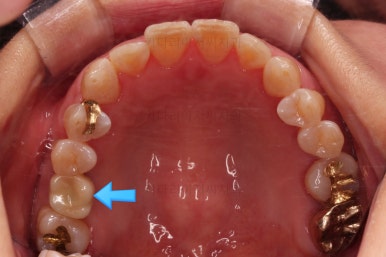

임플란트 머리 부분까지 완성이 되었어요.

교정치료와 임플란트치료를 병행해서 치아 빠진 부위가 다행히 잘 마무리가 되었네요.

부산교정치료 전후사진을 비교해 보겠습니다.

쓰러진 치아도 원위치로 만들어 기능을 회복시켜주었고, 임플란트도 1개로 마무리를 할 수 있었어요.

이렇게 단순히 임플란트를 해야 하는 상황도 간단한 교정치료와 병행한다면 치아도 아끼고 임플란트도 줄이는 매우 좋은 치료가 될 수 있답니다.